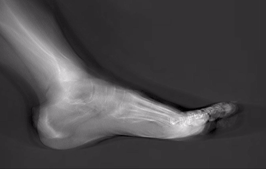

При томосинтезе длинных трубчатых костей значительно эффективнее оказываются полостные образования, возможным становится выявление переломов в локализациях, недоступных для классической рентгенографии.

Томосинтез позволяет визуализировать состояние внутрикостного канала длинных трубчатых костей, состояние кортикального и компактного слоев длинных трубчатых костей, места прикрепления капсулы и экстра-артикулярных связей в области суставов. При нарушении целостности кости томосинтез позволяет визуализировать развитие костной мозоли в зоне повреждения независимо от вида фиксации поврежденной конечности (гипсовая повязка, лангет, и т.д.). На получаемых изображениях четко визуализируется форма, размер и состояние кортикального слоя позвонков форма, размер и деструктивные изменения в суставах информативные как при дегенеративных, так и при системных поражениях.